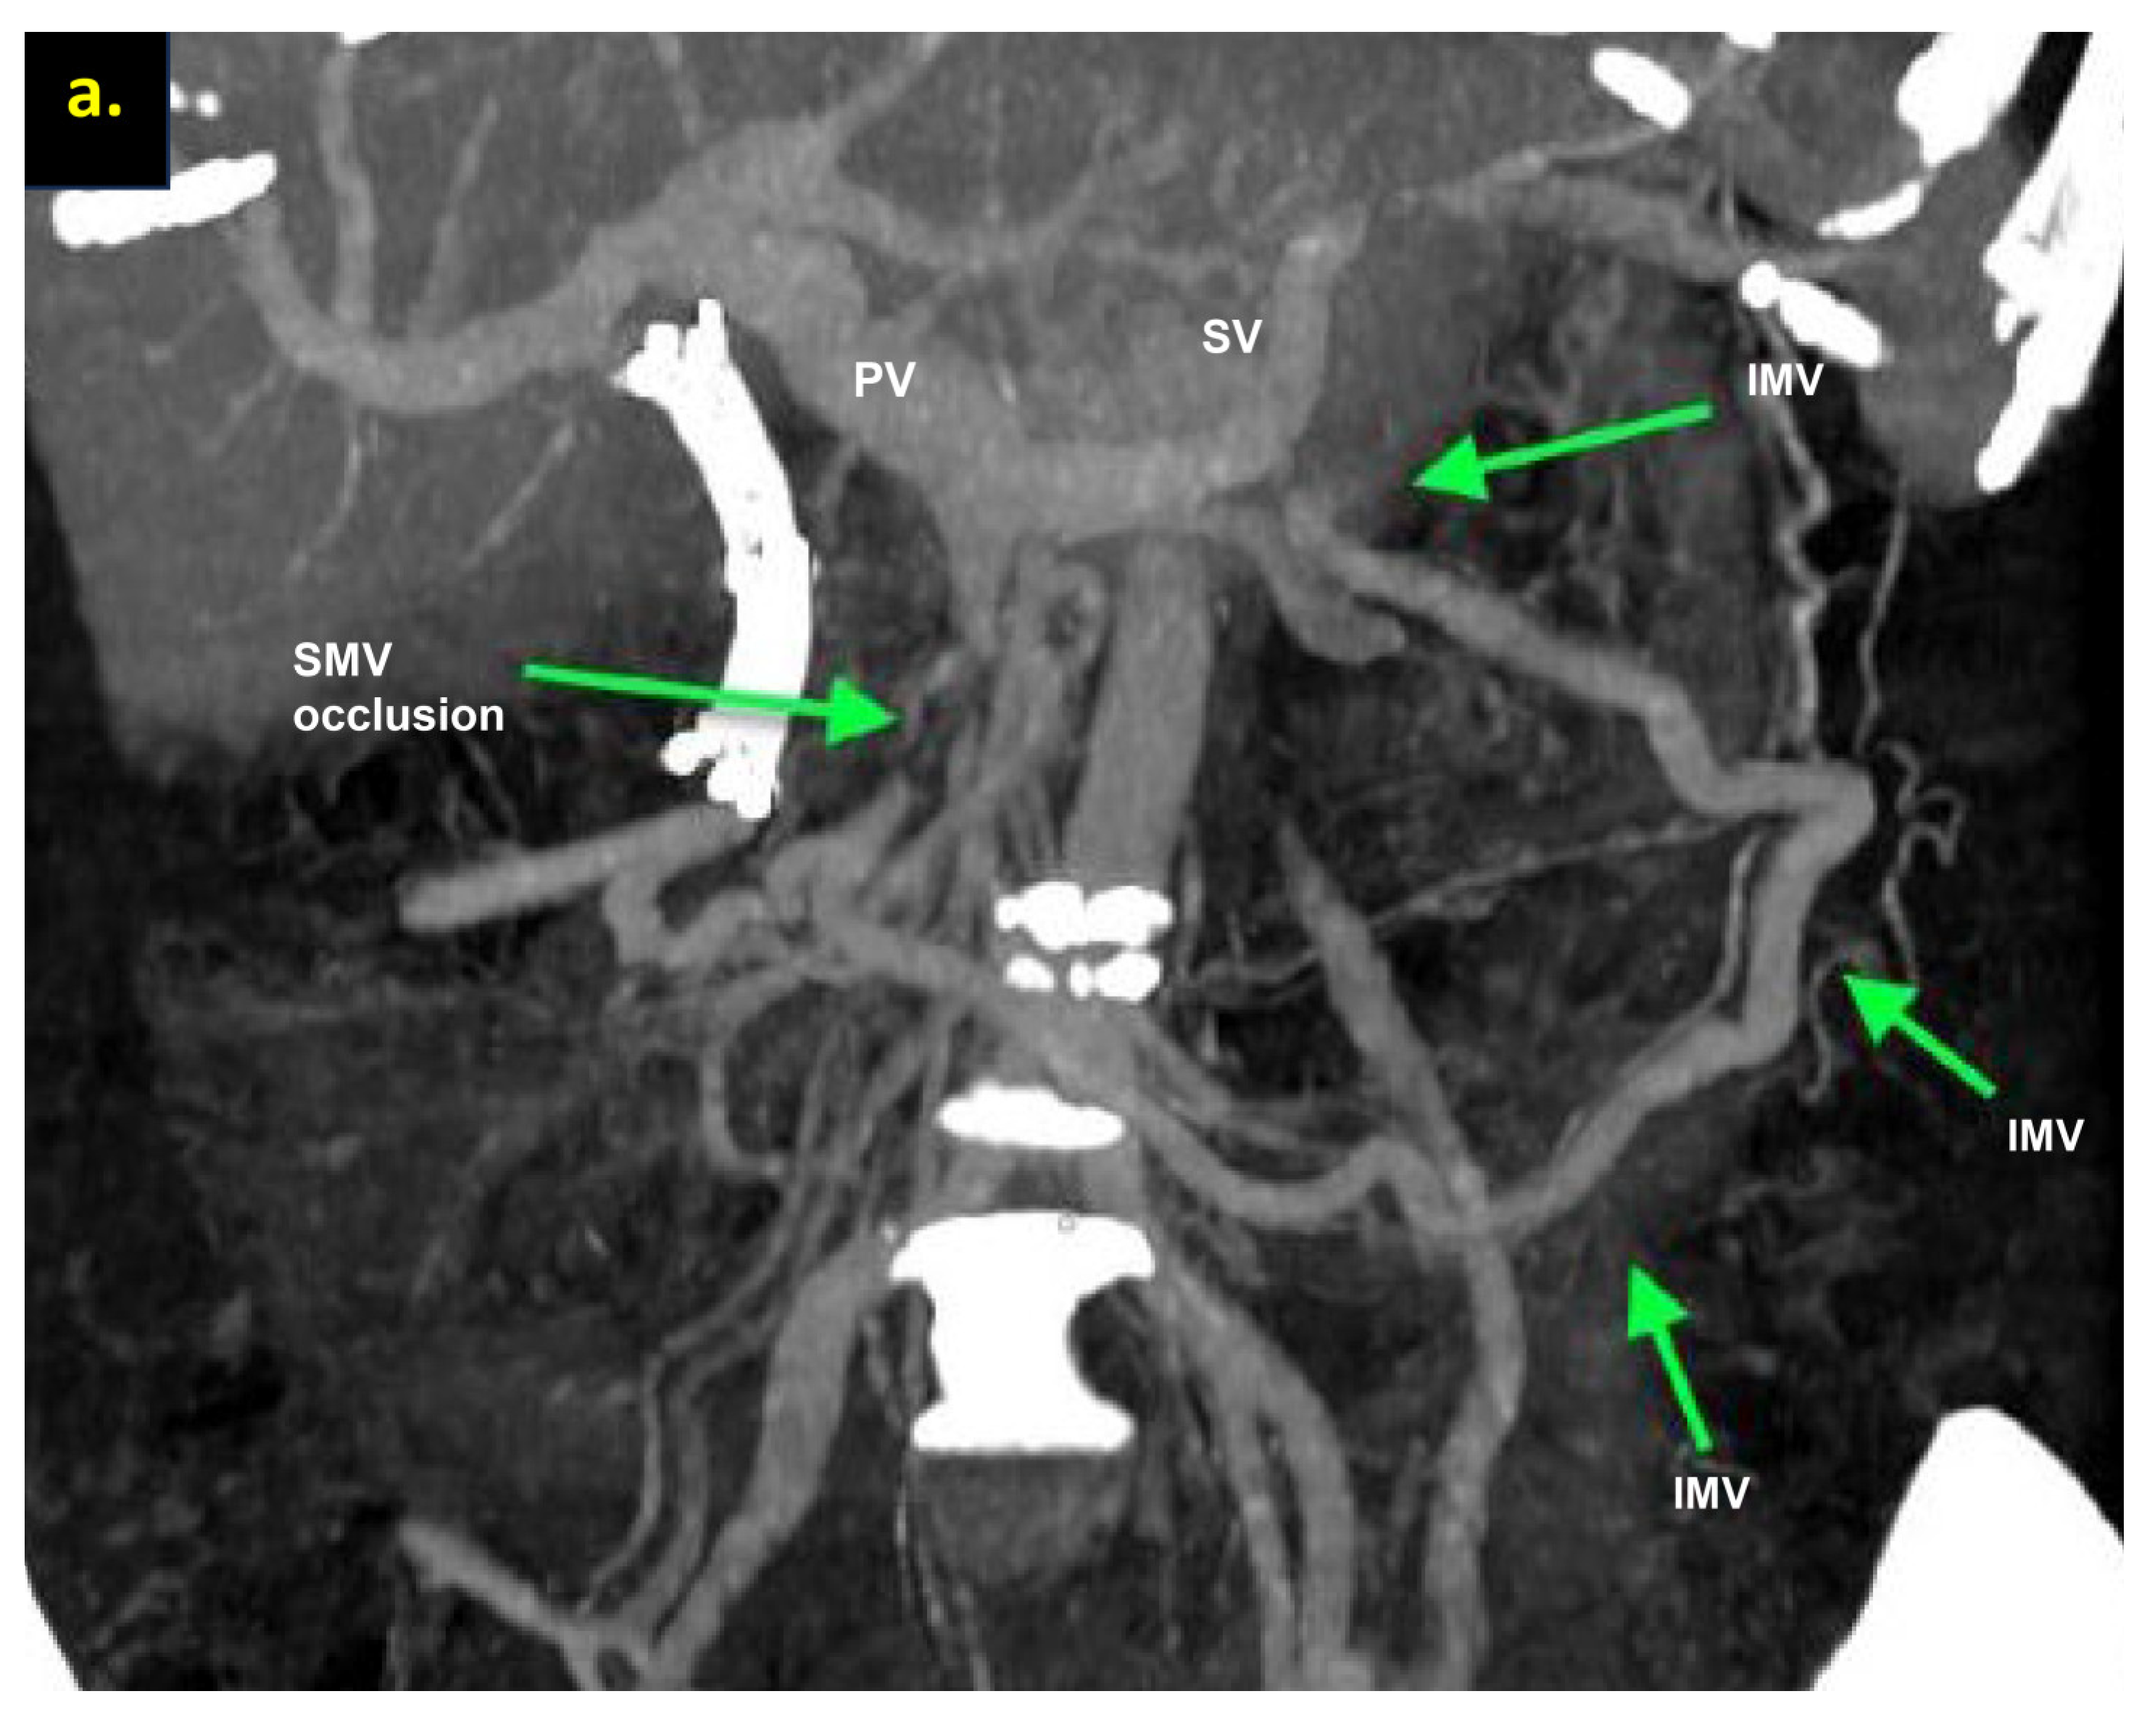

The combination of CT, MRI, PET/CT, and blood CA 19-9 was used as the best modality for the selection of candidates for radical surgery in patients with LA PDAC [11] by the evaluation of vascular involvement and distant metastases. Interpretation of the standardized digital images from the preoperative multiphase pancreatic MDCTs, MRIs, and PET/CTs (when available) of all 19 patients was independently performed by three abdominal image readers (PP, AD, EK). High-quality CT-based pancreatic protocol was the standard method of the anatomical resectability assessment with the analysis of four phases: native, arterial (pancreatic), portal venous, and delayed phases following high concentrated (350–400 mg/mL) non-ionic iodinated contrast media injection at the rate of 2.5–5.0 mL/s. CT examinations were performed between 2006 and 2024, using 32- to 256-detector scanners Philips Ingenuity, Philips iCT, GE optima CT 540, Philips Brilliance CT, Philips iCT, Toshiba Aqullion, and GE Revolution, with machine-specific image acquisition ranging from 0.625 to 3 mm axial slice thickness. Since 2008, 3D abdominal vein reconstructions have become useful and necessary components for decision-making on possible radical surgery for “low” pancreatic cancers with SMV thrombosis/involvement (Figure 1a–d). After ruling out the distant metastases, only patients with specific vein anatomy can be candidates for radical surgery. The mandatory anatomical conditions for the procedure were the following: (1) preserved SMV-SV confluence; (2) occluded SMV for any reason (tumor or thrombus); (3) well-developed inferior mesenteric vein (IMV) collaterals with dilated intestinal veins; (4) no right-sided vein collaterals (which will be sacrificed); and (5) no varices in the upper abdomen.

Figure 1.

Post-processing reconstructions of MDCT portal phase images for adenocarcinomas of the pancreatic uncinate process, associated with SMV occlusion, caused by its thrombosis and/or involvement. Three-dimensional maximum intensity projections (MIP) and volume-rendered (VR) imaging show preserved SMV-SV confluence, occluded SMV, well-developed IMV collaterals with dilated intestinal veins, and the absence of right-sided vein collaterals and varices. (a) Three-dimensional MIP reconstruction shows the dilated SMV tributaries, gastro-epiploic venous arcade (GEVA), left gastric (LGV), and inferior mesenteric veins (IMV) flowing into the splenic vein (SV); (b) three-dimensional MIP reconstruction. Dilated gastro-epiploic vein (GEV), and IMV anastomosing with the SV; (c) three-dimensional VR reconstruction. SMV is thrombosed and surrounded by the tumor; (d) three-dimensional VR reconstruction shows the dilated SMV tributaries and IMV flowing into the splenic vein (SV). The tumor shrank after chemotherapy, the SMV is occluded and the narrow left SMV is going along it. PV-portal vein. Abbreviations correspond to all the figures.

We used different post-processing CT techniques for the assessment of the peripancreatic vessels and collateral venous blood flow adequacy, such as shaded surface display, maximum intensity projection, and 3D volume-rendered (VR) reconstruction imaging. Now, when planning SMV resection with excision of all its tributaries for “low” pancreatic cancer, we consider CT-based 3D-VR reconstruction the best and most necessary option for the depiction of the collateral venous system. Compared to the other rendering CT techniques, VR is superior in delineating vessels, pancreatic parenchyma, the tumor, and adjacent structures (Figure 1a–d, Figure 5a,b, Figure 6a,b and Figure 7a,b,d) [43,44,45].